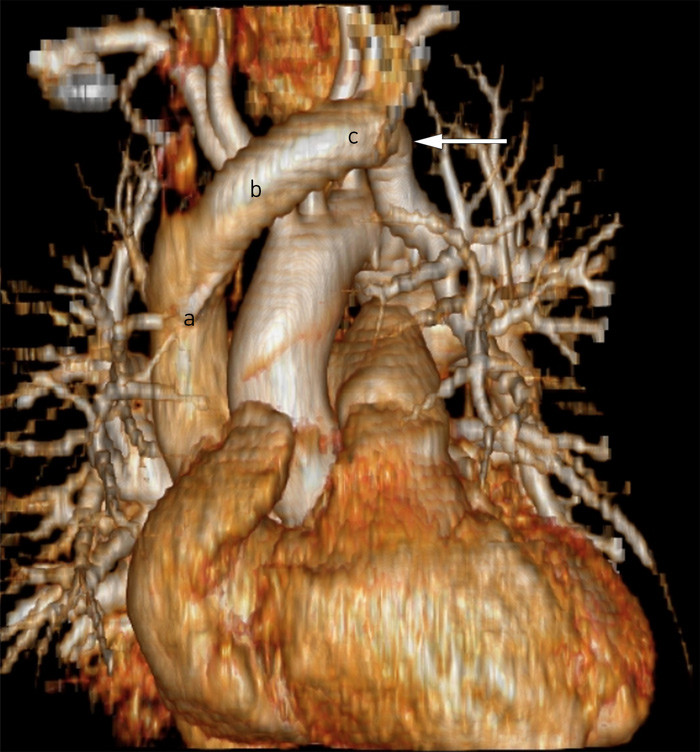

Pasienten ble respiratorbehandlet i totalt åtte døgn pga. respirasjonssvikt. Hun ble på overvåkingsavdeling ytterligere seks dager pga. svært dårlig allmenntilstand og utvikling av hjertesvikt med dyspné, pleuravæske og deklive ødemer. Ved overflytting til sengepost var hun fortsatt kraftløs og med behov for parenteral ernæring. Flere kirurgiske tilsyn og bildediagnostikk konkluderte med paralytisk ileus. På sengepost ble det pga. rubor rundt innstikkstedet lagt et nytt sentralt venekateter. Første forsøk på innstikk, nå via venstre v. jugularis interna, ble avbrutt fordi anestesilegen fikk lyst rødt blod tilbake ved aspirasjon og antok at han hadde kommet inn i en arterie. Nytt innstikk ble gjort under ultralydveiledning, og man så da ingen spor etter blødning fra eventuell perforasjon av arterie. I ettertid er det rimelig å anta at også første forsøk var vellykket, men at uventet aspirasjon av arterielt farget blod ble feiltolket av en lege som ikke kjente til pasientens forhistorie. Blodprøver tatt fra dette tredje kateteret, der spissen vurdert røntgenologisk lå på samme sted som nr. 2 (fig 1), viste vedvarende tilnærmet identiske verdier venøst som prøver tatt arterielt, rundt 95 %. Pasienten ble derfor henvist til CT angiografi for å avklare mistanken om sentral arteriovenøs shunt. Undersøkelsen påviste en sjelden anatomisk anomali der venstre pulmonalvenes ene gren drenerte direkte til tverrvenen, vena brachiocephalica sinistra (fig 2, fig 3). Det var gjennom innleggelsen tatt flere røntgen thorax, men ingen av disse kunne gi mistanke om en slik anomali.

Anomalien fører til at godt oksygenert blod fra lungen dreneres inn til venesystemet. Funksjonelt tilsvarer dette oksygeneringsmessig en stor venstre-til-høyre-shunt, noe som forklarte funnet av flere tilnærmet like SO₂-verdier i arteriell og venøs blodgass.

Ved revurdering av tidligere ekkobilder (både transøsofageale og transtorakale), fant man på grunnlag av beregning av minuttvolum fra henholdsvis høyre og venstre ventrikkel at høyre ventrikkels minuttvolum lå ca. 34 % over venstre ventrikkels. I tillegg så man antydning til forhøyet trykk i høyre ventrikkel med avflating av septum i diastolen. CT-bildene viste også en dilatert venstre v. brachiocephalica med diameter 18 mm, som er ca. 50 % større enn normaldiameter. Dette stemmer bra med vesentlig øket strøm gjennom karet.

Partiell, avvikende pulmonalvenekobling (partial anomalous pulmonary venous connection, PAPVC) er en sjelden, medfødt anomali, med insidens på 0,4 – 0,7 % (5, 6). Anomalien innebærer oftest at en (eller flere) pulmonalvene(r) er koblet til høyre atrium eller v. cava i stedet for til venstre atrium, slik at oksygenert blod strømmer tilbake til høyresiden, dvs. analogt med en venstre-til-høyre-shunt på hjertenivå. Isolert partiell, avvikende pulmonalvenekobling (uten atrieseptumdefekt) er en sjelden tilstand, og innebærer oftest at øvre høyre pulmonalvene drenerer til v. cava superior. Anomalien som vår pasient hadde, med affeksjon av venstre pulmonalvene med drenasje til venstre v. brachiocephalica, affiserer ca. 3 % av alle med partiell, avvikende pulmonalvenekobling (5). Således er dette en svært sjelden anomali. Symptombildet er avhengig av hvor mange pulmonalvener som drenerer til høyresiden av hjertet. En enkelt avvikende vene er sjelden av hemodynamisk betydning og gir dermed oftest ingen symptomer (5), men representerer likevel en økt belastning på høyre ventrikkel.

Det første kateteret lå lengst distalt i v. cava superior, slik at man kunne tenke seg at kraftig refluks fra en atrieseptumdefekt kunne gi den høye ScvO₂-verdien. De to neste katetrene lå imidlertid mer proksimalt i v. cava superior, og en høy sentralvenøs metning herfra kan vanskelig forklares av en slik årsak (fig 1).